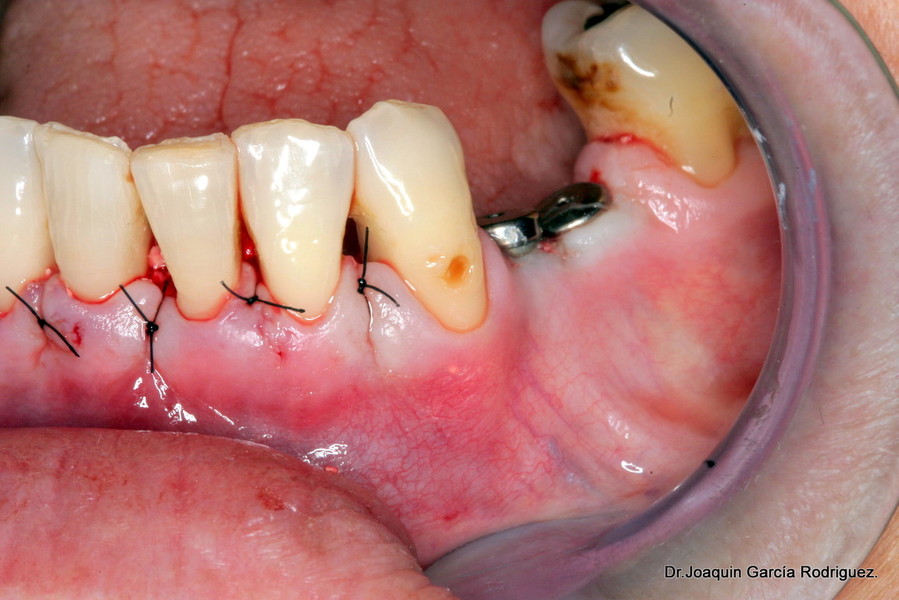

Una vez analizados los datos estableceremos un plan de tratamiento. Iniciando el plan de tratamiento periodontal, con cirugías de widman modificado por la técnica de ramfjiord, relleno de los defectos óseos, inserción de implantes y diseño de la prótesis.

En este caso nos decidimos por las coronas de circonio, ya que si se produce una recesión gingival, jamás se evidenciará el metal.